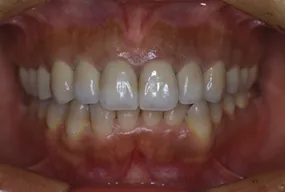

治療完了時

| 患者様のお悩み | 外傷で歯が抜けた |

| 治療法・使用素材 | インプラント治療の後、セラミック治療 |

| 患者様の年代 | 20代 |

| 治療開始年齢 | 20代 |

| 治療にかかった期間 | 8か月 |

| 性別 | 女性 |

| この治療のリスクについて | インプラントが正しい位置に入るかどうか |

| 治療にかかった費用 | 45万円 |